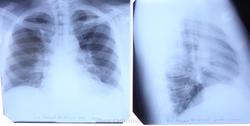

Средостенье смещено несколько вправо.нет? и легкое будто бы ротировано?

На мой взгляд, средостение не смещено. ///легкое будто бы ротировано?/// А что такое "легкое ротировано"? И признак чего это?

Корни легких расширены, полицикличны

Я бы поставил базальный пневмосклероз. Увеличение ЛЖ. Р - картина лимфоаденопатии . и рекомендованно Кт с контрастом. а они уже разберутся.

Средостение посерёдке.О ротации лёгких слышу впервые.Здесь неструктурны корни,усилен рисунок в прикорневых зонах.Согласуйте с клиникой.

Доля непарной вены справа по-видимому?

Доля то доля..., а вот только ли "доля"?

Ага, корни неструктурные, расширенные, и может кажется обеднение легочного рисунка на периферии.. диф. диагноз между лимфаденопатией и сердечнососудистой патологией

Согласен с Вами, Валентин Львович. Мне непонятно, что это за контур такой дугобразный, от верхушки до диафрагмы. На долю непарной вены не тянет.